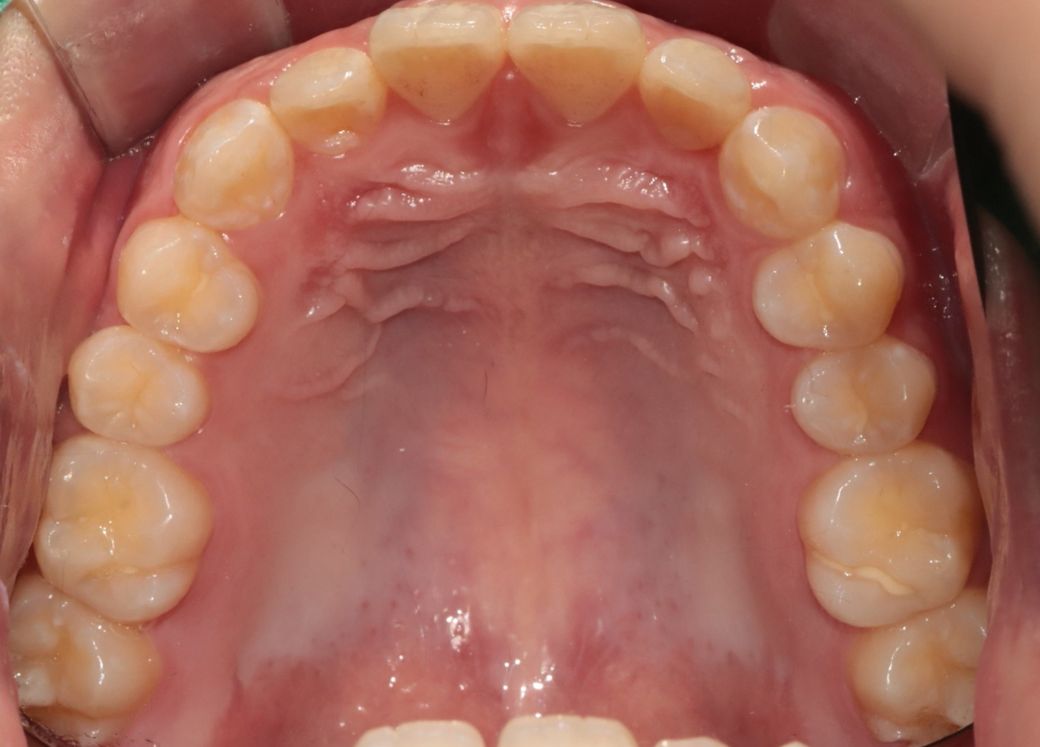

A치과) 상악에 비해 하악이 긴편이나 정상범위라고 볼수 있어 주걱턱은 아니라고 봅니다. 그래서 수술적 치료는 필요치 않아 보입니다. 치아상태는 전치부 총생 및 전방경사가 있고 상악 우측절치 반대교합이 있다 장기적으로는 좋지못하다. 앞니 부분교정 또는 인비절추천